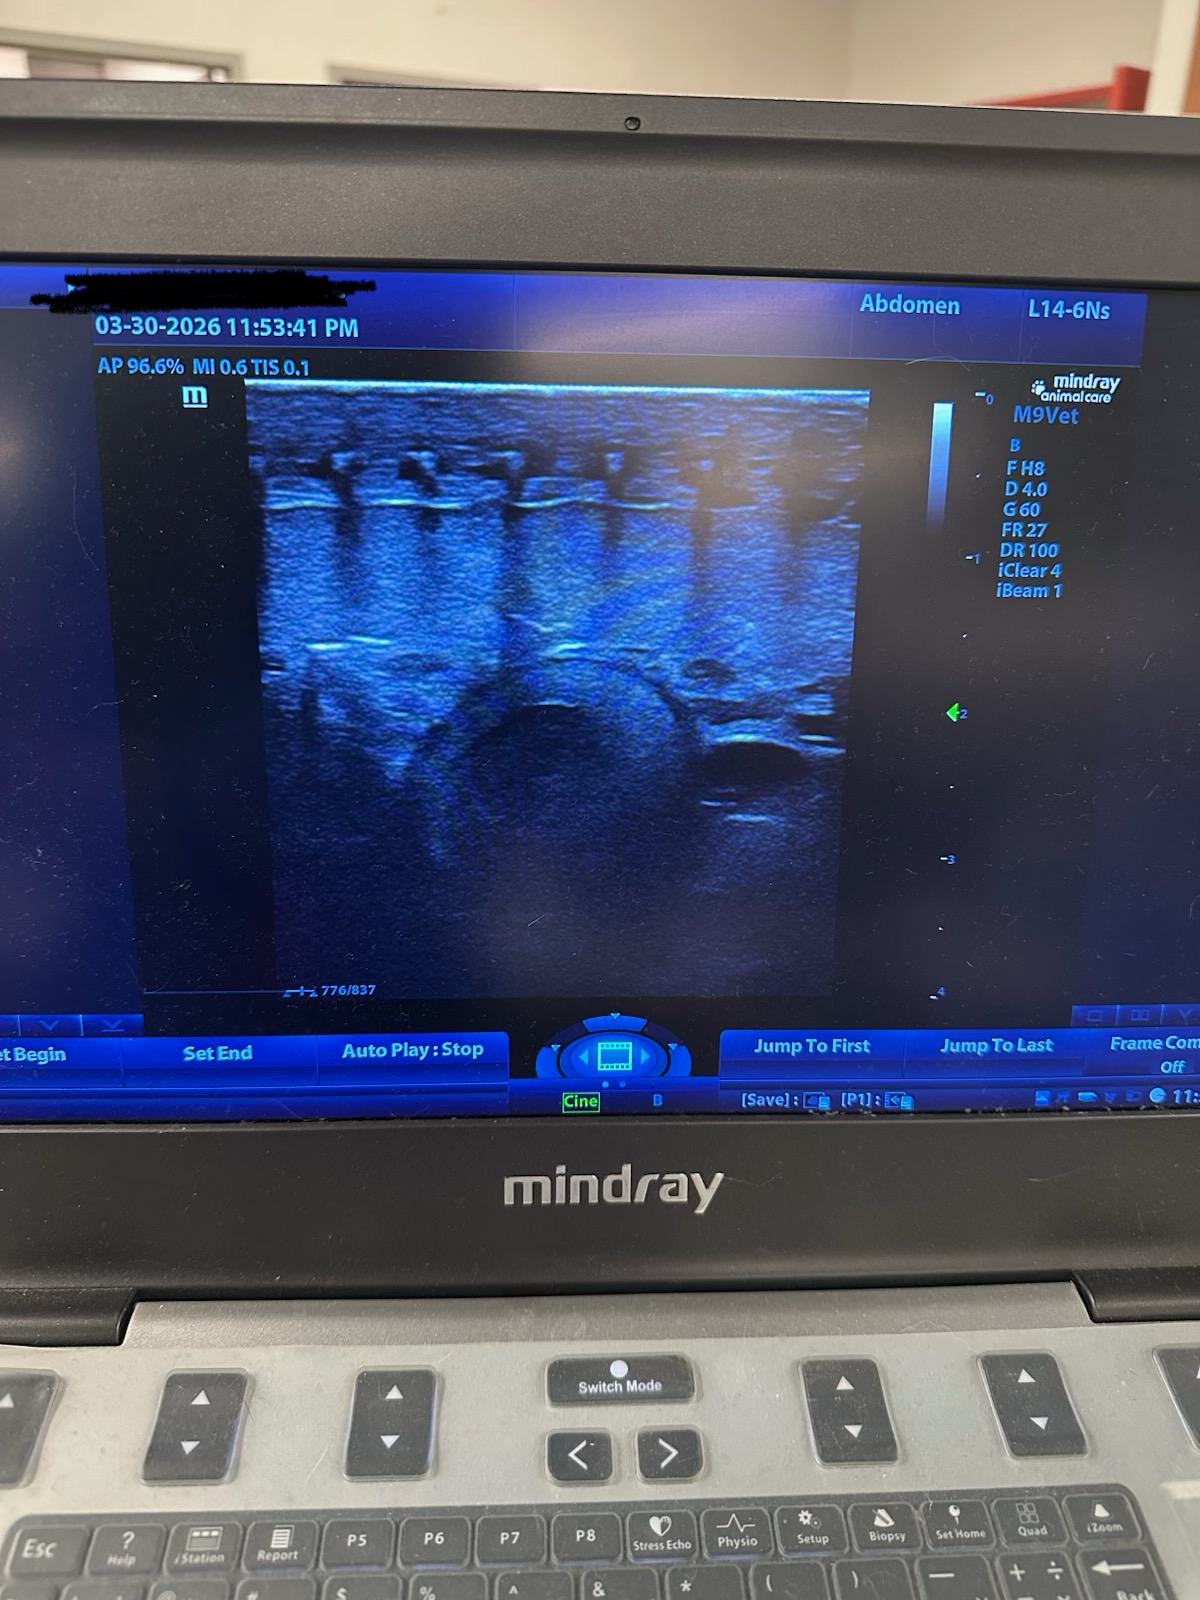

Not very familiar with reading ultrasounds but took this while at work… Is this a follicles

???

So I took the image and marked what I see.

On the lower end, it does appear that there are 2, possibly 3 follicles that are maturing… the lower one furthest to the right I’m unsure of.

The smaller marked spots that are higher up I believe are follicles as well, that haven’t begun the maturation process yet.

Well, there are usually more than one follicle developing at a time. Did you save video of the ultrasound or just this one still? Did you see a chain of them one after the other, like around 6 of them?